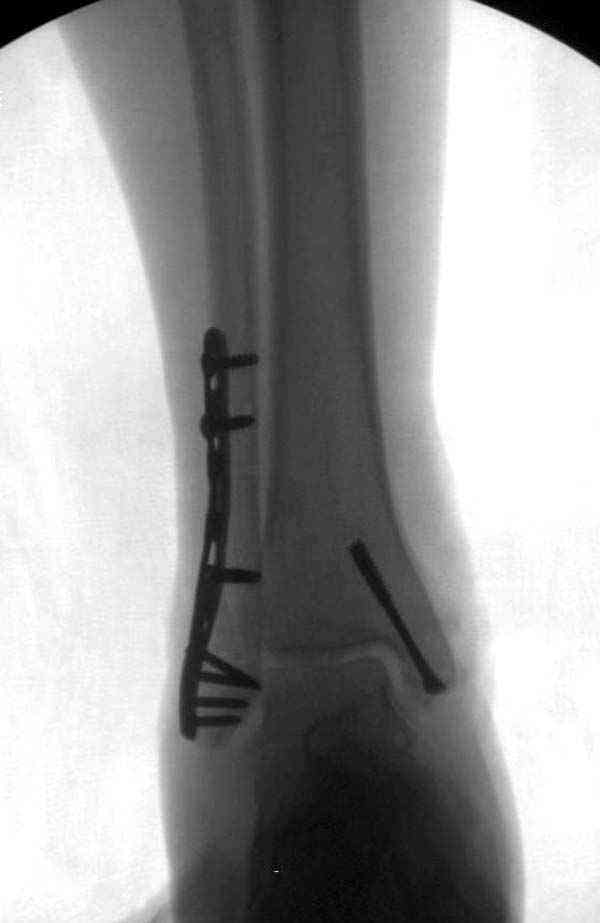

Описанная вами техника "Внутренняя лодыжка фиксирована по Веберу, наружная реконструктивной пластиной с наложением болта-стяжки" существует, но этот подход морально устарел, и применяется очень редко, только при отсутствии имплантов.

Нет первичных снимков, перелом очень низкий и под большим сомнением диагноз разрыва синдесмоза. Медиальная сторона отрепонирована на "хорошо" и, по-видимому, прорезание проволоки произошло во время операции. Без снимков трудно судить о высоте малоберцовой, а лодыжка находится в варусе. Лагирование получилось, но возле тонких шурупов передне-задний шуруп выглядит немного тяжеловато.

Здесь несколько частных случаев: перелом голеностопа со сравнительными снимками и разрыв синдесмоза, а также медиальная Hook пластина.